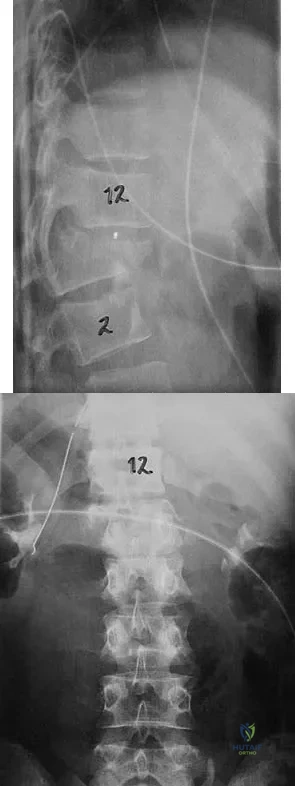

Figures 27a and 27b show the radiographs of a 32-year-old woman who was involved in a high-speed motor vehicle accident. She is neurologically intact. After stabilization and assessment, treatment should consist of

Explanation